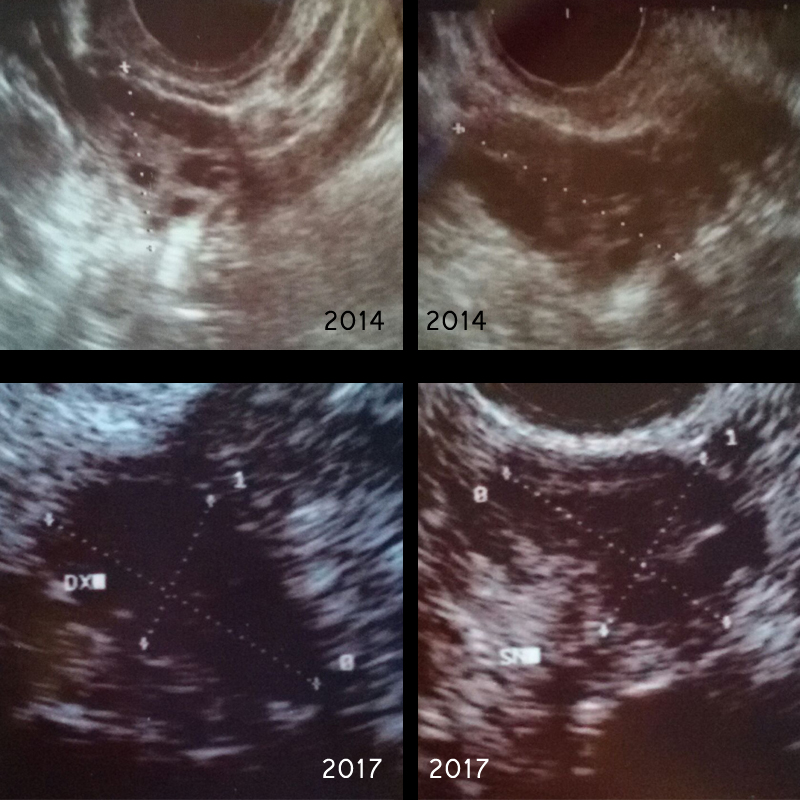

nel 2014 mi è stato diagnosticato l'ovaio micropolicistico. Sto curando il problema (e l'acne che ne deriva), con Belara. Attualmente sono ad un anno e sette mesi di cura. Recentemente ho fatto un nuovo controllo. Il medico che ha eseguito l'eco, ha riscontrato l'assenza di qualsiasi formazione cistica, e guardando i vecchi esami, ha sostenuto addirittura che non vi siano mai state.

Posto qui le immagini delle eco del 2014, e quelle dell'ultimo controllo. Qual'è la verità a riguardo? Posso interrompere il trattamento con Belara?

Commento file: Ecografie 2014 e 2017